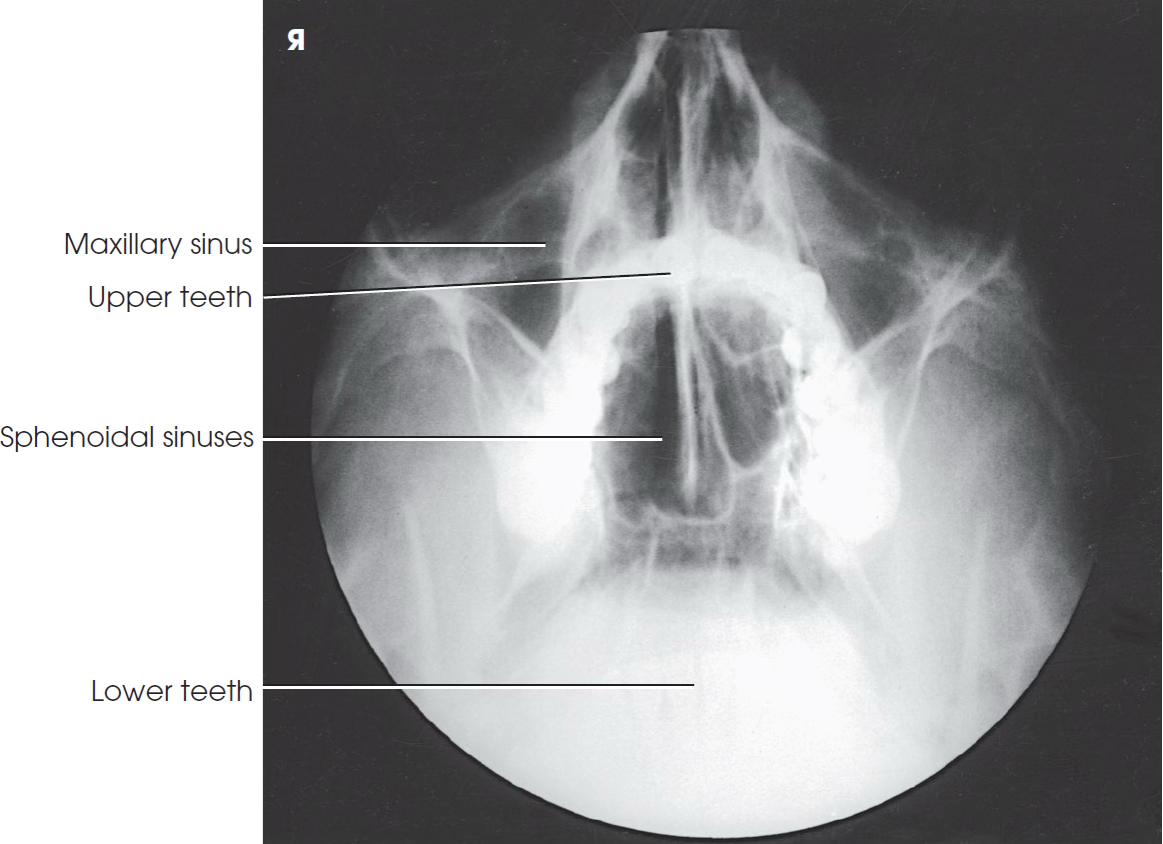

Open mouth waters

Open Mouth waters part position

Same as Waters; mouth open

Open Mouth waters central ray

Horizontal exiting acanthion

Waters Open Mouth sinus demonstrates ___

Sphenoid sinus